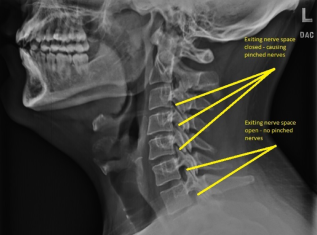

Digital X-Ray

At Dr. Asher Natural Chiropractic We have a new state of the art digital X-ray machine that is able to accomodate patients from all walks of life. We pride ourselves in the identification and treatment of spinal disorders, but we are also able to accomodate and evaluate upper and lower extremities with our advanced tilting X-ray bucky.